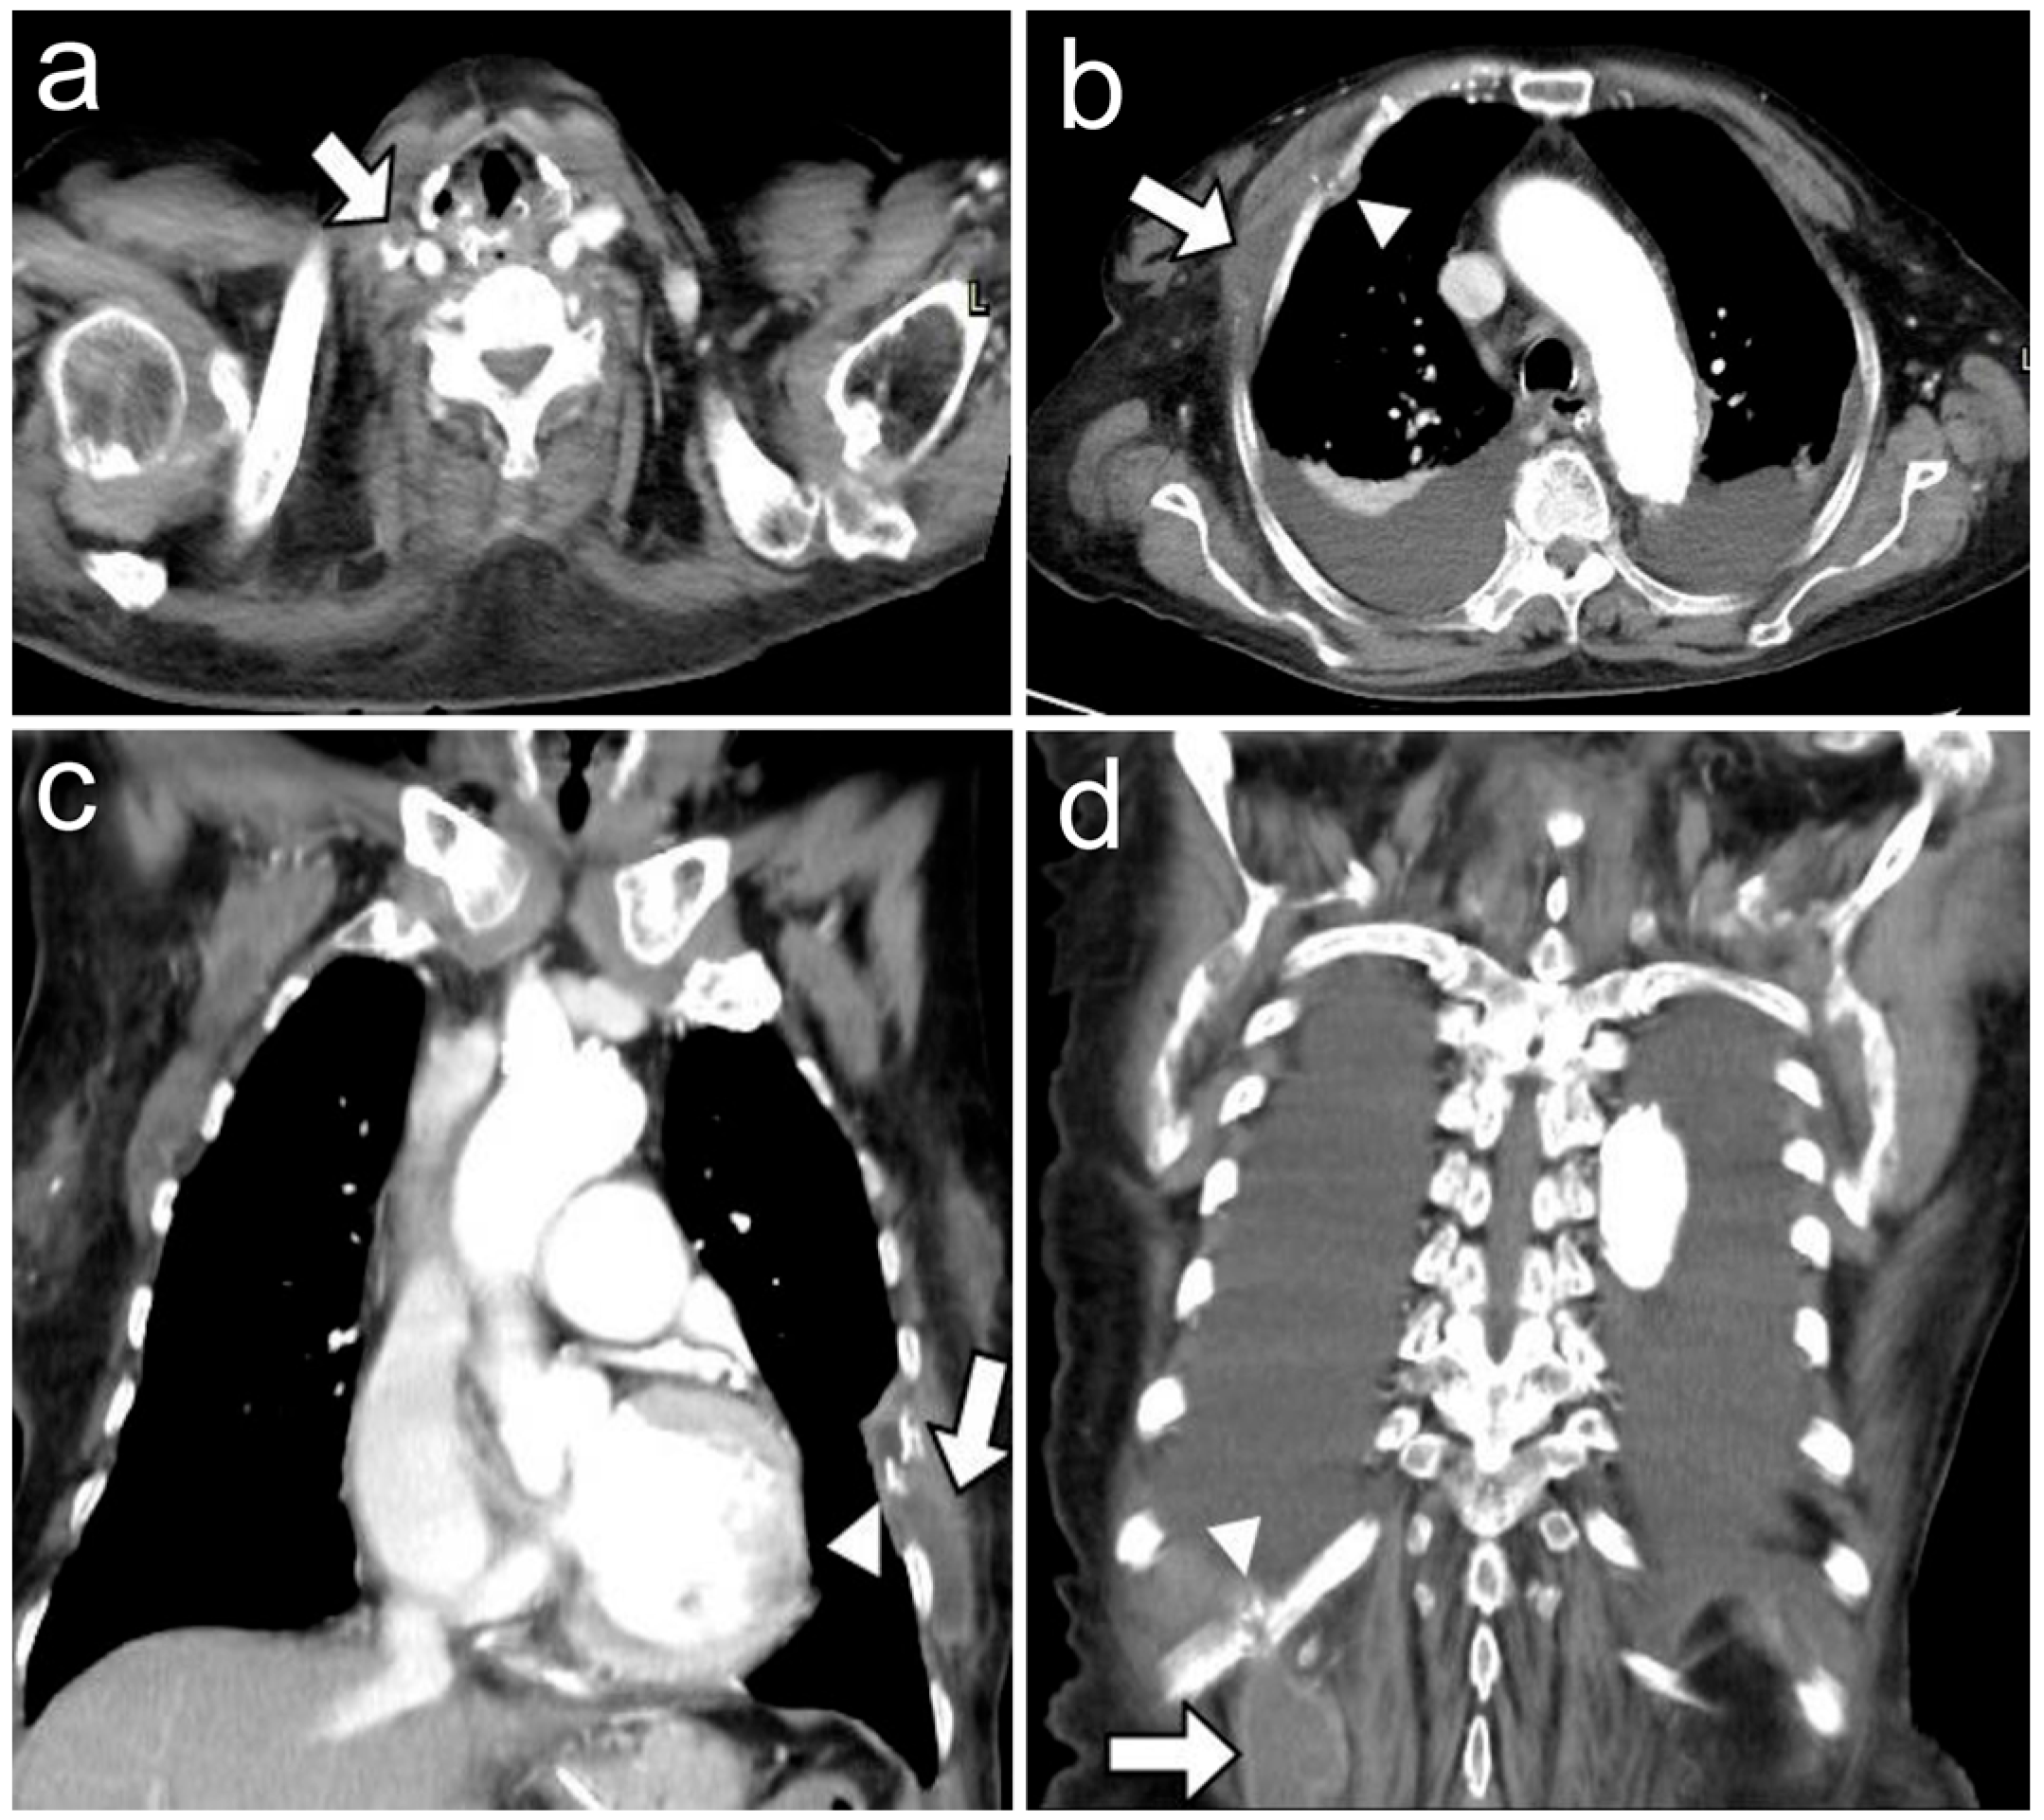

Multiple Cold Abscesses of a Chest Wall with Ribs Destruction in a Hemodialysis Patient